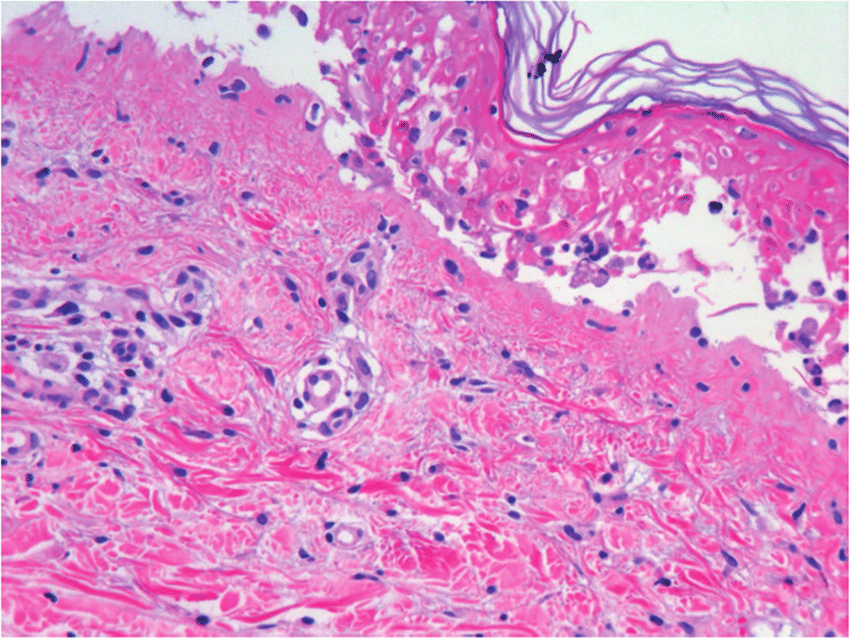

La enfermedad de la piel inducida por fármacos o las reacciones cutáneas adversas a fármacos (RAMc) son términos que engloban las manifestaciones clínicas de la piel, las mucosas y los anexos inducidas por un fármaco o sus metabolitos. El reconocimiento de una reacciones cutáneas adversas a fármacos específica dependerá principalmente de la capacidad del médico para realizar un examen clínico detallado, la descripción adecuada de la morfología de las lesiones cutáneas y los hallazgos de laboratorio y/o biopsia de piel que respalden. Br J Clin Pharmacol, 16 de agosto de 2022

Drug Saf, 24 de abril de 2019Las reacciones adversas cutáneas a los medicamentos son impredecibles e incluyen varias afecciones cutáneas diferentes de diversos grados de gravedad.  Todas son reacciones de hipersensibilidad de tipo IV retardadas en las que una respuesta inmune específica de un fármaco mediada por células T es responsable de causar la enfermedad. No obstante, las subpoblaciones específicas de células T se desarrollan en respuesta a ciertas condiciones ambientales y producen citocinas que orquestan los diversos fenotipos.